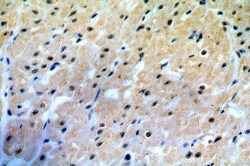

19420-1-AP IHC

Immunohistochemistry